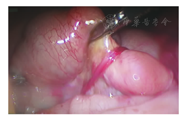

NEC并发的肠狭窄系继发性肠狭窄,任何引起新生儿肠管损伤和肠系膜血管缺血的原因,均可导致肠狭窄甚至肠闭锁。肠内肌层的缺血性损伤在NEC后肠狭窄的发病中起重要作用[1,5]。多数学者认为继发性肠狭窄是血栓及炎症造成的肠壁缺血性损伤修复的结局,尤其是既往有肠道炎症性疾病的患儿,局部肠道炎症反应导致胶原沉积、纤维化和伤口收缩,形成肠腔的狭窄或完全性梗阻[1,6]。也有观点认为机械性压力可能是部分继发性肠狭窄及闭锁的发生机制。如肠粘连带、肠管及其系膜供血血管被索带压迫,导致肠壁的供血中断,肠壁缺血坏死、炎症及重吸收最终发展成肠狭窄或闭锁[7]。本研究中狭窄位于回肠的患儿,狭窄部位的肠管与周围组织多有不同程度的粘连或索带压迫(图2)。肠壁局部血供障碍、持续炎症和坏死组织吸收,三者共同作用继而发生肠狭窄甚至出现肠闭锁[8]。